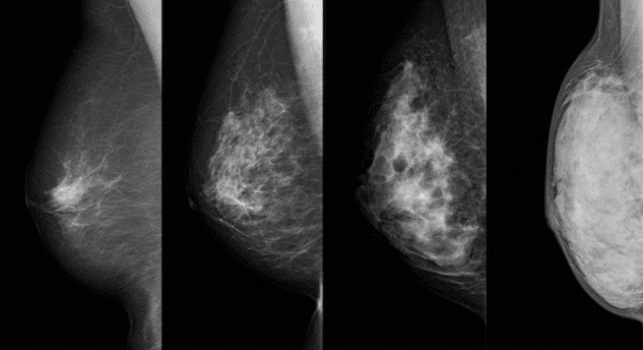

Ce cours sera l’occasion pour les participants, médecins généralistes, chirurgiens, radiologues, oncologues, radiothérapeutes, psychologues, de débattre des récentes évolutions en matière de diagnostic et de traitement du cancer du sein.